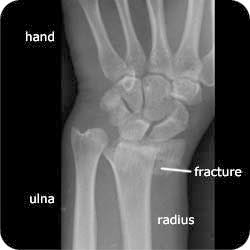

Basically… my radius is broken at the joint, and is off set from where it should be. The end of my radius, where the joint is, is cracked in half. Bones are rubbing together and not in the places they should be (this is after being “reset” last Thursday.)

So…. I have surgery scheduled for Friday morning to have a plate and screws put in my wrist. I will have to do weekly therapy and will be unable to ride for 6-8 weeks He said it could be 6 months to a year before I’m feeling full function of my wrist again. Good times, I tell ya!!